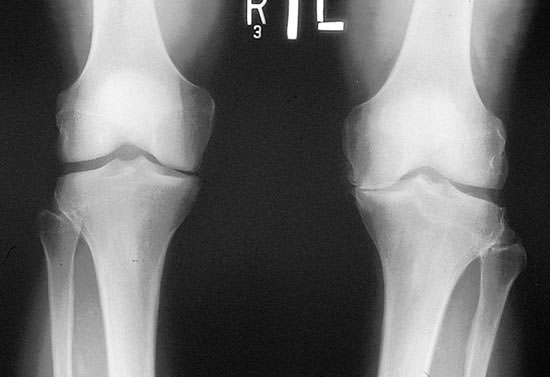

Приходько В.И. врач, МГМСУ, г. Москва По мнению профессора В.В. Поворознюка, Остеоартроз – наиболее распространенная...

На сегодняшний день существует огромнейшее количество заболеваний, связанных с суставами. Медицине известны разные формы заболеваний,...

Приходько В.И. врач, МГМСУ, г. Москва По мнению профессора В.В. Поворознюка, Остеоартроз...

В.И. Приходько, МГМСУ, Г. Москва По мнению профессора В.В. Поворознюка, Остеоартроз –...

Е.В. Приходько, доцент, г. Москва Остеоартроз (АО) гетерогенная группа заболеваний различной этиологии,...